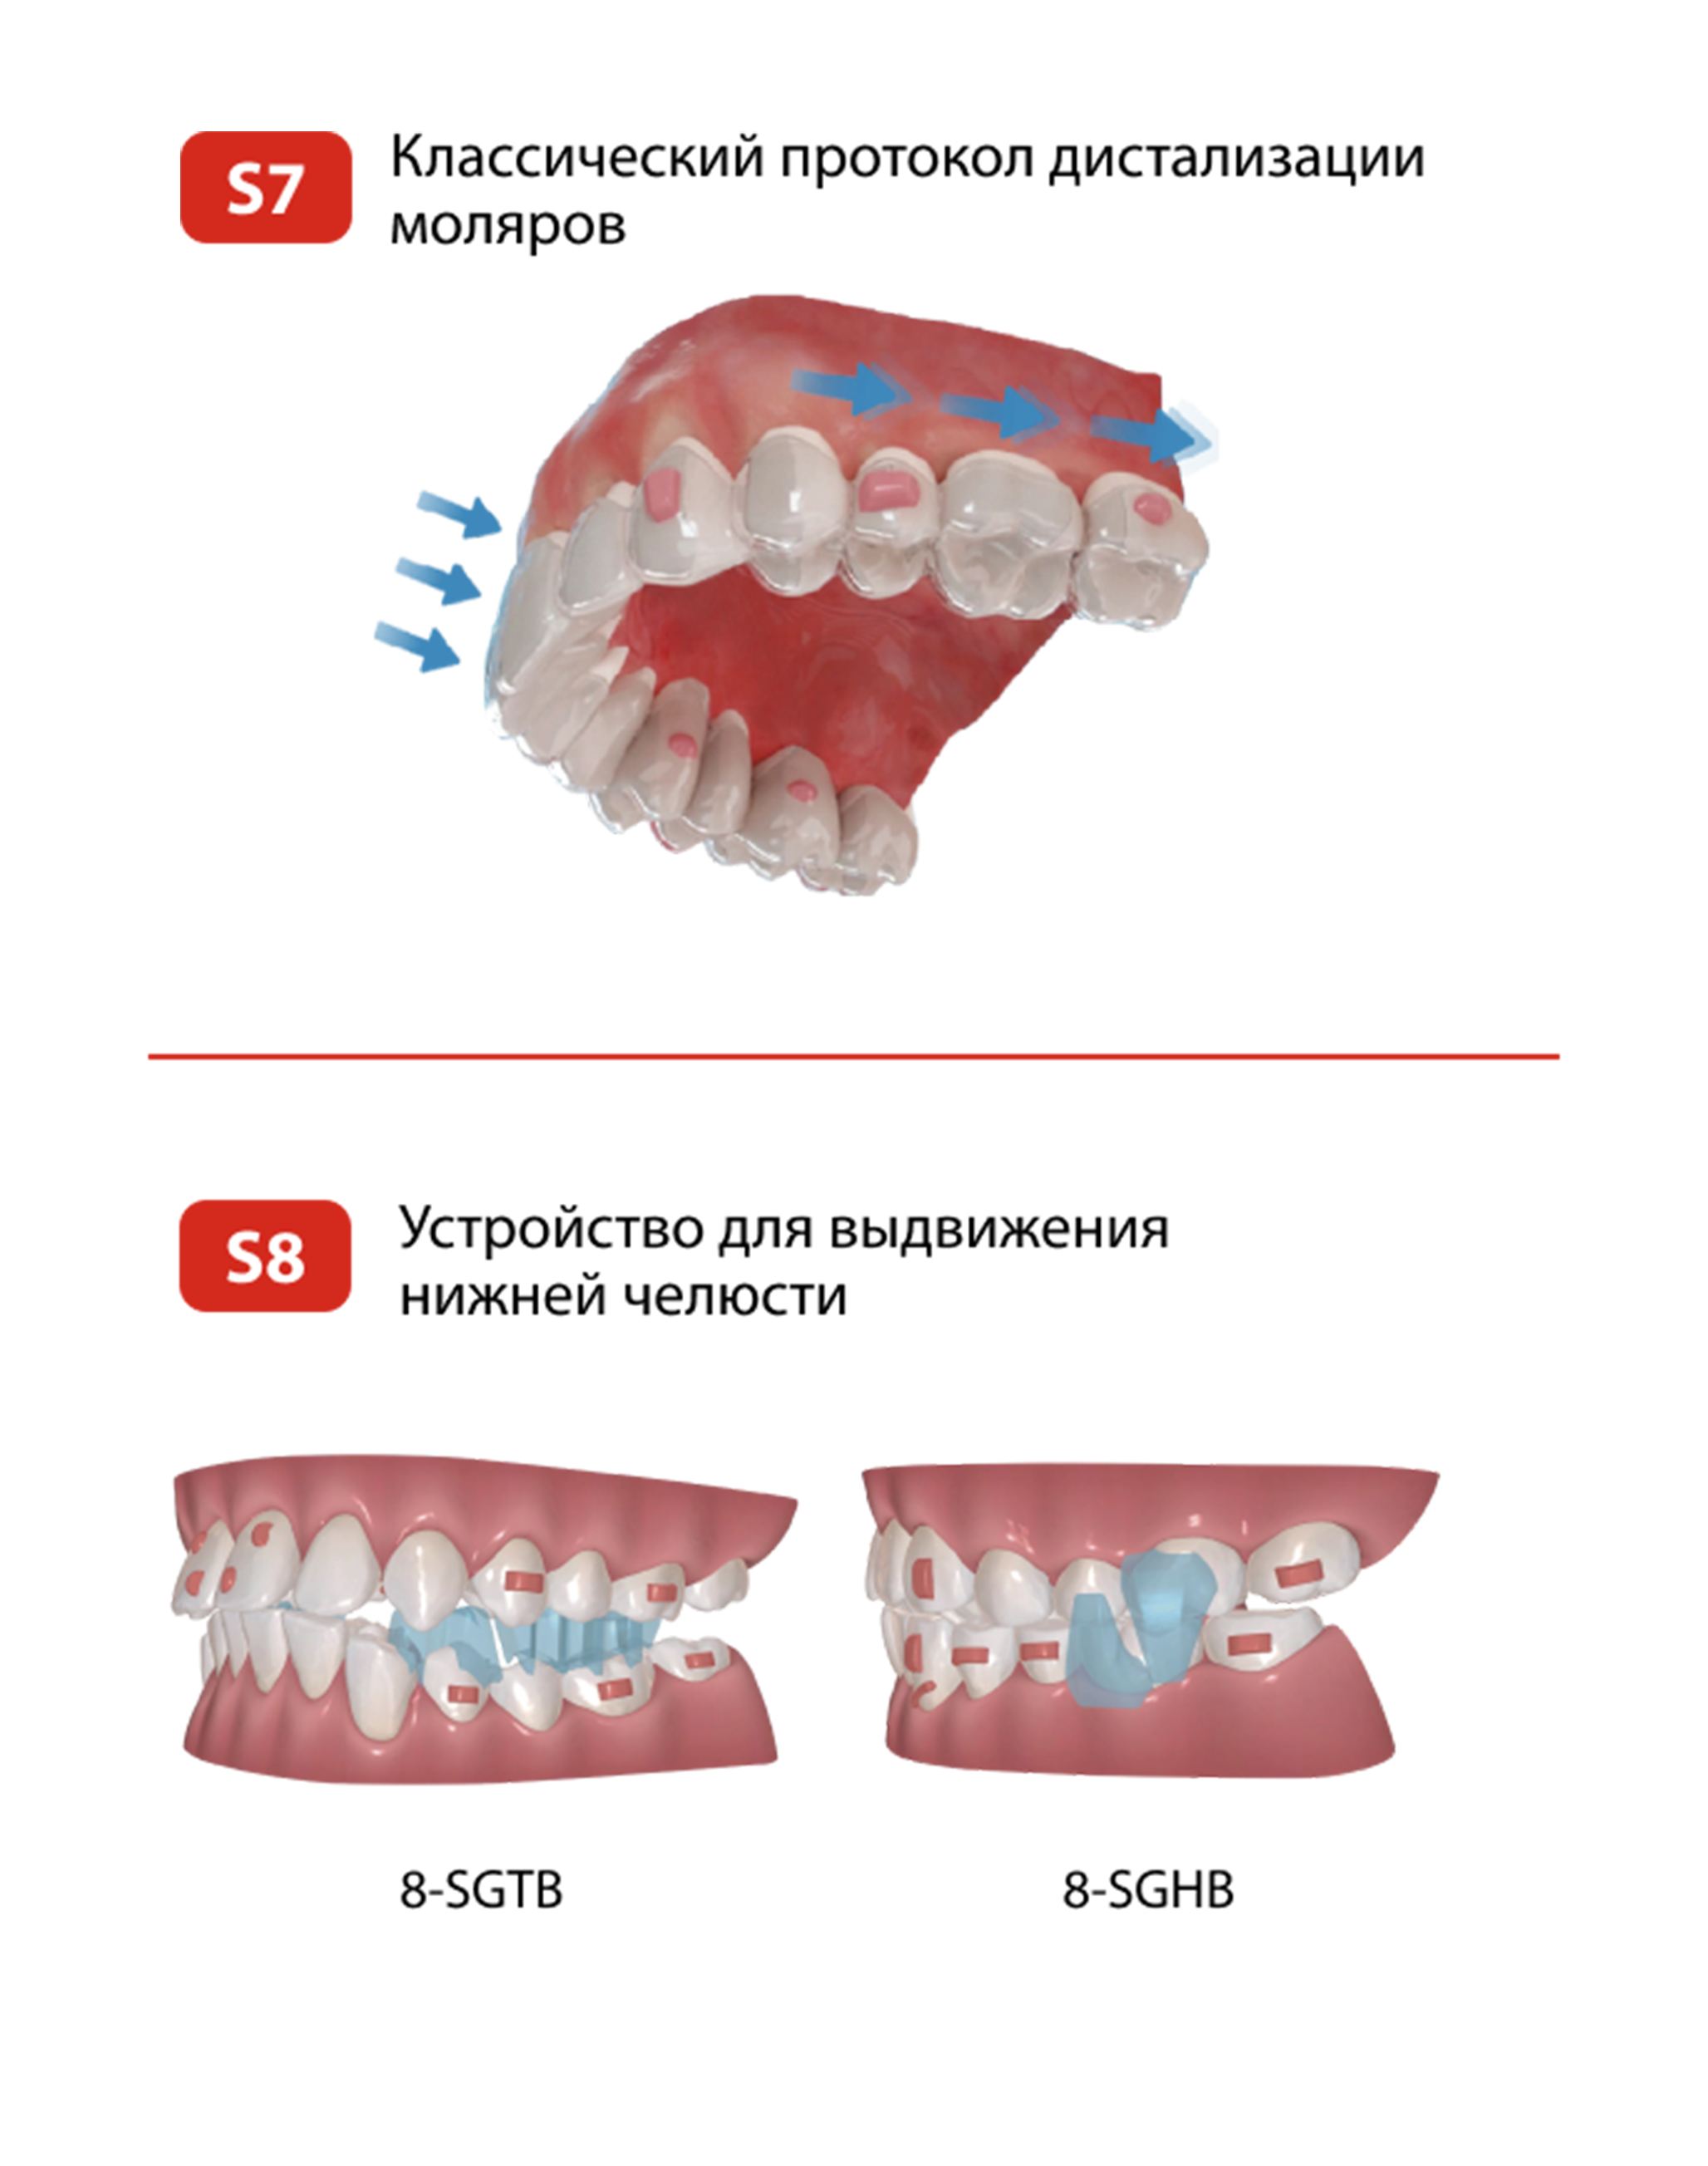

ТРЁХСЛОЙНАЯ ТЕХНОЛОГИЯ ПРОИЗВОДСТВА ПЛАСТИН

C 2006 года мы опробовали материалы множества производителей и к 2016 году

приняли решение взять контроль качества на себя и открыть собственное производство

Трёхслойная технология производства пластин